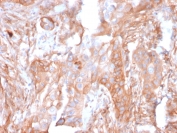

IHC staining of FFPE human lung carcinoma with CD73 antibody (clone NT5E/2503). HIER: boil tissue sections in pH9 10mM Tris with 1mM EDTA for 10-20 min and allow to cool before testing.